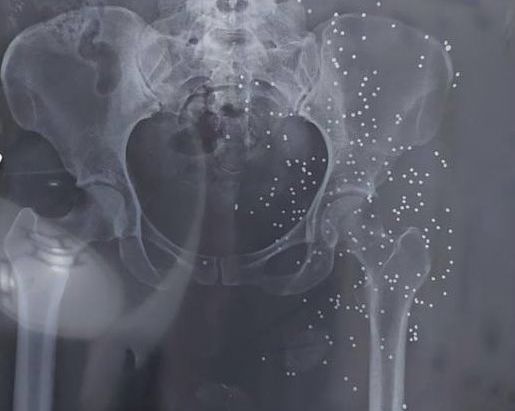

It did not provide names, dates or locations for the photos, which mainly are from injuries that protesters sustained from shotgun pellets as well as bruises and fractures caused after being beaten by the security forces. Most of the photos and videos are so graphic that cannot be republished by Iran International.

In addition to photos and videos of the injuries, the batch includes dozens of x-ray images and CT scans of pellets and slugs in the head, neck, chest and legs of the protestors. The Islamic Republic has killed many protesters with rubber bullets and metal pellets and blinded so many others.

The regime’s security forces have been extensively using cartridges of shotshell loaded with numerous small balls or birdshots, or medium-sized buckshots as well as single large solid projectiles known as a slug to quash the nationwide protests, ignited by the death in custody of 22-year-old Mahsa Amini in September 2022.